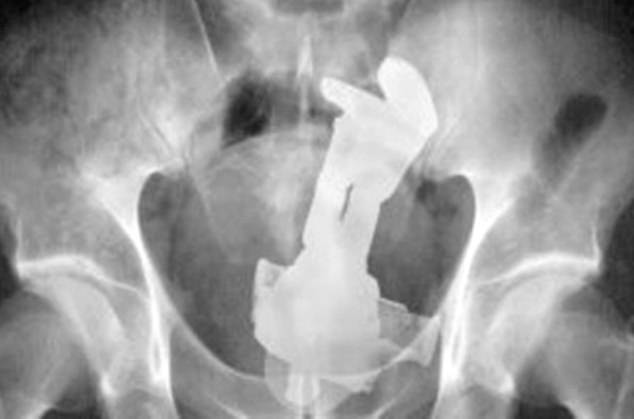

▼至於體內發現各種形狀的成人玩具,對急診室醫生來說已經見怪不怪了!